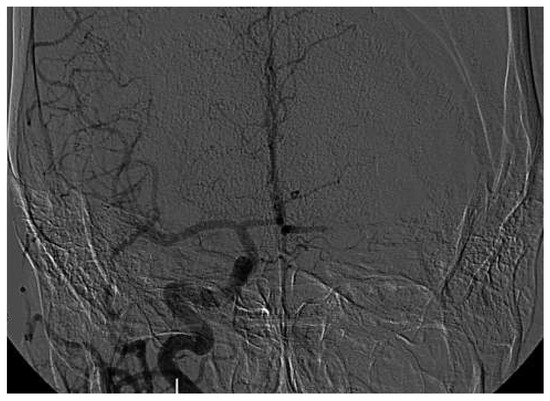

Mechanical Thrombectomy After Embolic Internal Carotid Artery Occlusion in Acute Stroke

Case presentation